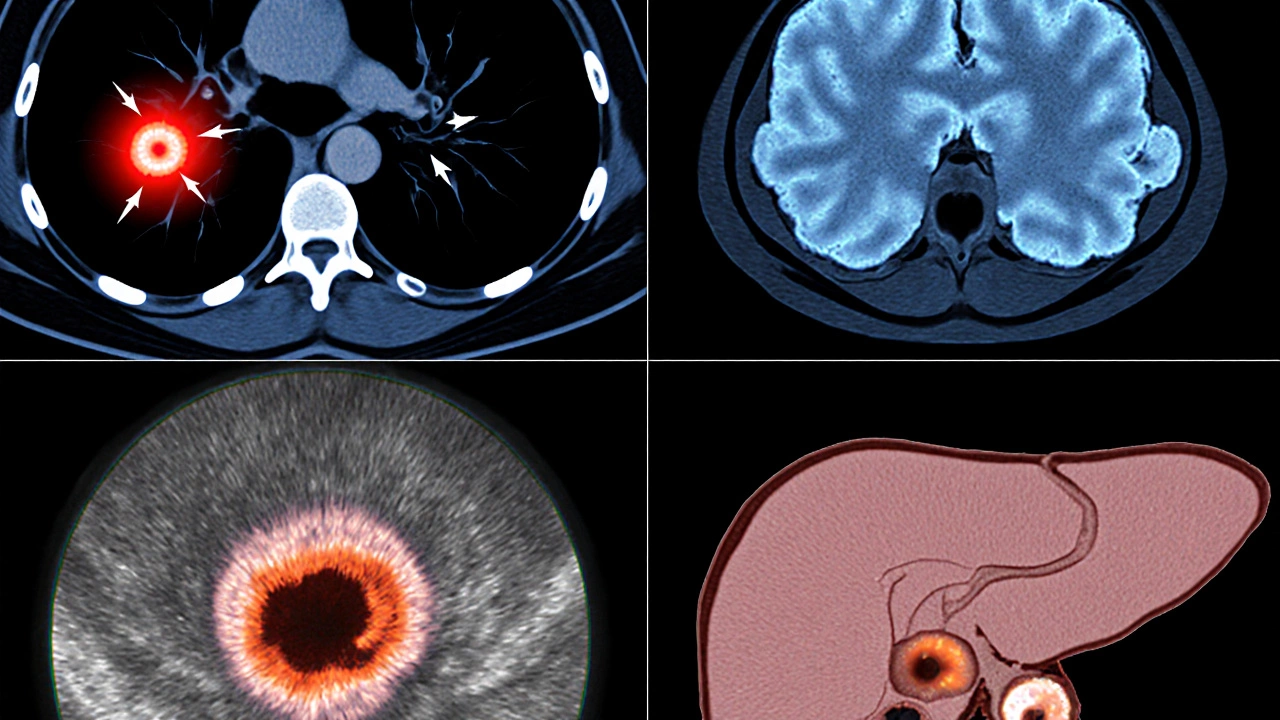

Top Cancers With the Lowest Five‑Year Survival

The following list gathers the cancers that consistently rank at the bottom of survival charts. Each entry includes the latest survival data, typical stage at diagnosis, and why outcomes are so grim.